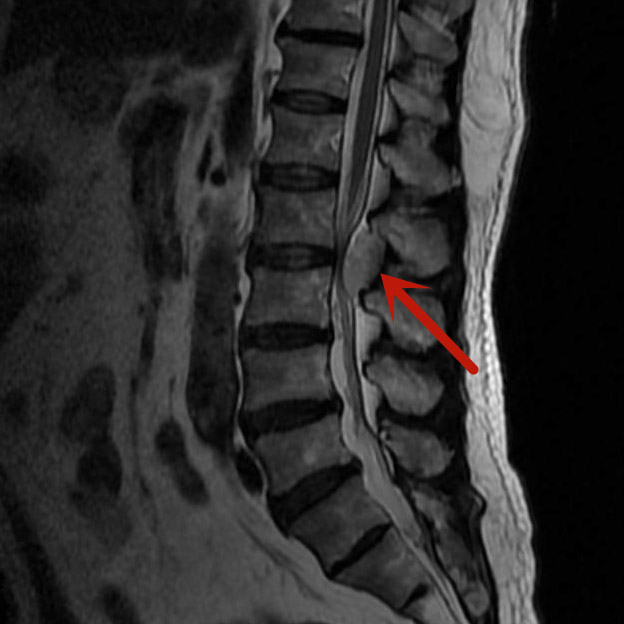

梁先生因雙下肢麻木來我院就診,經(jīng)磁共振檢查發(fā)現(xiàn)是腰椎管內(nèi)血管瘤在作怪,若不及時手術(shù)治療,隨著腫瘤的生長、神經(jīng)長時間受壓,將可能導(dǎo)致雙下肢癱瘓、大小便失禁等嚴(yán)重后果。

經(jīng)我院脊柱骨科醫(yī)療團(tuán)隊研究后,決定對梁先生實施內(nèi)鏡下腰椎管內(nèi)腫瘤切除術(shù),腫瘤約3.5cm×1.5cm大小,別看腫瘤不大,但要完全通過0.8cm大小切口在內(nèi)鏡下切除,腫瘤后方的椎板切除減壓、腫瘤與周圍神經(jīng)的分離、腫瘤的暴露、腫瘤的徹底切除,這都需要嫻熟的內(nèi)鏡操作技術(shù)。

在完善術(shù)前檢查,排除手術(shù)禁忌,充分做好術(shù)前準(zhǔn)備后,由微創(chuàng)手術(shù)經(jīng)驗豐富的醫(yī)師主刀,經(jīng)過兩個小時,完整將腫瘤切除。梁先生術(shù)后第一天便可下床活動,四天后即康復(fù)出院。